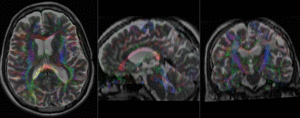

| DTI and T2 before & after registration (click to enlarge) |